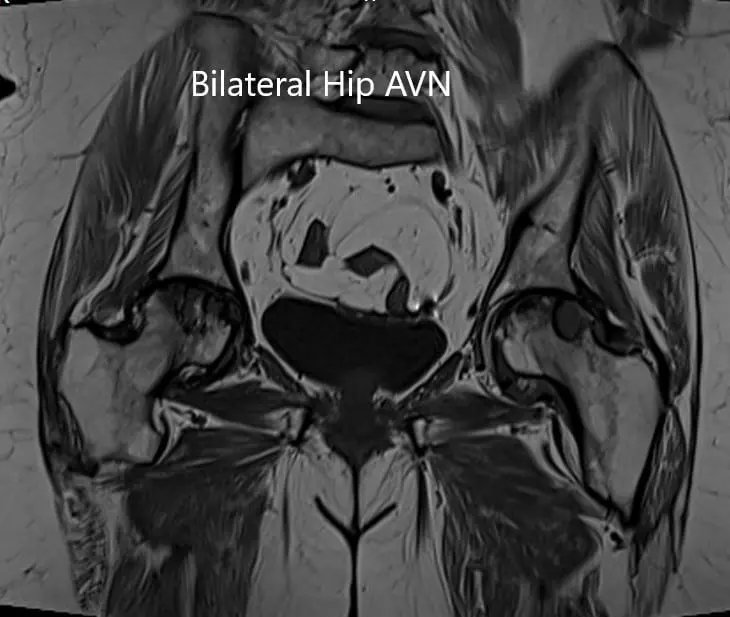

MRI was obtained which showed:

Right Hip Joint: There is a loss of sphericity of right femoral head, involving more than 2/3 of the circumference. In the superior part of the right femoral head, a focal lesion is visualized which is bounded by a serpiginous T1 hypointense margin. The lesion is hypointense on both T1 & T2WI relative to the marrow (Mitchell class – D).

No subchondral fracture is detected. A minimal amount of fluid is seen in the joint cavity. The femoral neck and acetabulum display normal signal intensity. Muscles in view display normal signal intensity.

Left hip joint: Displays similar although less severe changes. The sphericity of the left femoral head is maintained. There is more than 2/3 circumferential involvement of the left femoral head. No subchondral fracture is seen. No joint effusion is seen.

Axial sections of T1WI and T2WI of the pelvis MRI.